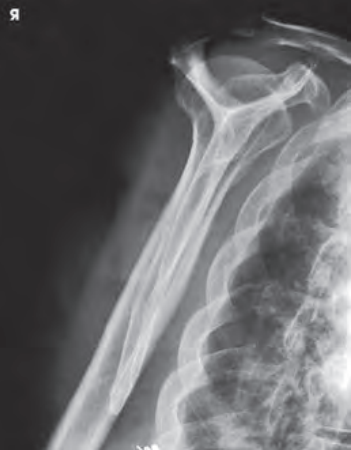

안녕하세요, 오늘은 어깨(shoulder) 촬영방법 중 하나인 shoulder Lateral oblique(Scapula Y view) 촬영법에 대해서 설명하겠습니다. 견갑골이 알파벳Y자로 보여 Y view라는 이름이 지어졌습니다. 이 촬영법은 어깨 dislocation(탈구)가 의심되는 환자 평가에 유용합니다.

영상평가

- body of scapula와 rib이 겹쳐지지 않게 한다.

- Coracoid process(오훼돌기)가 포함되어야 한다.

- 견갑골은 Y자 형상을 하여야 한다.

- 전방탈구의 경우 상완골두가 coracoid process아래에 위치한다

- 후방탈구의 경우 상완골두가 acromioclavicular process 아래에 위치한다